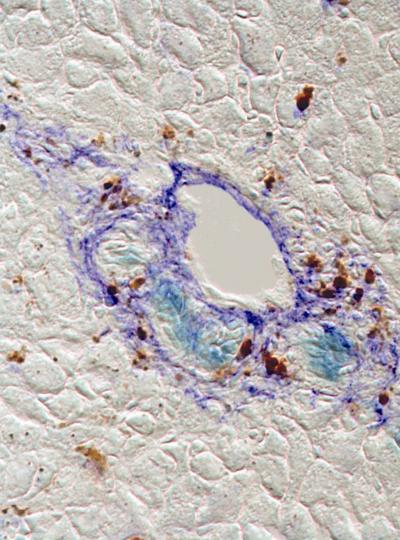

A novel protein marker has been found that identifies rare adult liver stem cells, whose ability to regenerate injured liver tissue has the potential for cell-replacement therapy. For the first time, researchers at the University of Pennsylvania School of Medicine led by Linda Greenbaum, MD, Assistant Professor of Medicine in the Division of Gastroenterology, have demonstrated that cells expressing the marker can differentiate into both liver cells and cells that line the bile duct. In the future, this marker will allow for the isolation and expansion of these stem cells, which could then be used to help patients whose livers can no longer repair their own tissue. About 17,000 Americans are currently on a waiting list for a liver transplant, according to the American Liver Foundation. The findings appear online this month in the journal Hepatology.

For chronic injury, the liver uses a back-up system that stimulates stem cells to proliferate and eventually differentiate into new liver cells. Greenbaum and colleagues found that these dual-potential stem cells can be identified and potentially isolated from other liver cells because they uniquely express the protein Foxl1. The team showed that in two mice models of liver injury, stem cells and their descendents were marked by the expression of FoxL1. The researchers propose to use this marker to isolate the Foxl1-bearing stem cells and transplant them back into damaged livers to restore function.